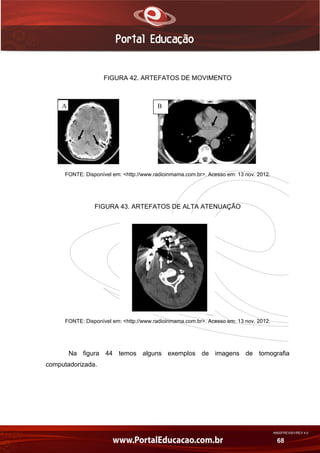

d) Os artefatos de imagem

Os artefatos de imagem são quaisquer estruturas ou padrões divergentes do

objeto de estudo. Os artefatos de imagem podem ser causados por uma infinidade

de fatores, os principais são: artefatos de movimento, causados tanto por

movimentos voluntários (Figura 42 A) quanto por movimentos involuntários do corpo

humano (Figura 42 B) e os artefatos de alta atenuação (Figura 43), como obturações

dentárias e outros objetos.

FIGURA 42. ARTEFATOS DE MOVIMENTO

FONTE: Disponível em: <http://www.radioinmama.com.br>. Acesso em: 13 nov. 2012.

FIGURA 43. ARTEFATOS DE ALTA ATENUAÇÃO